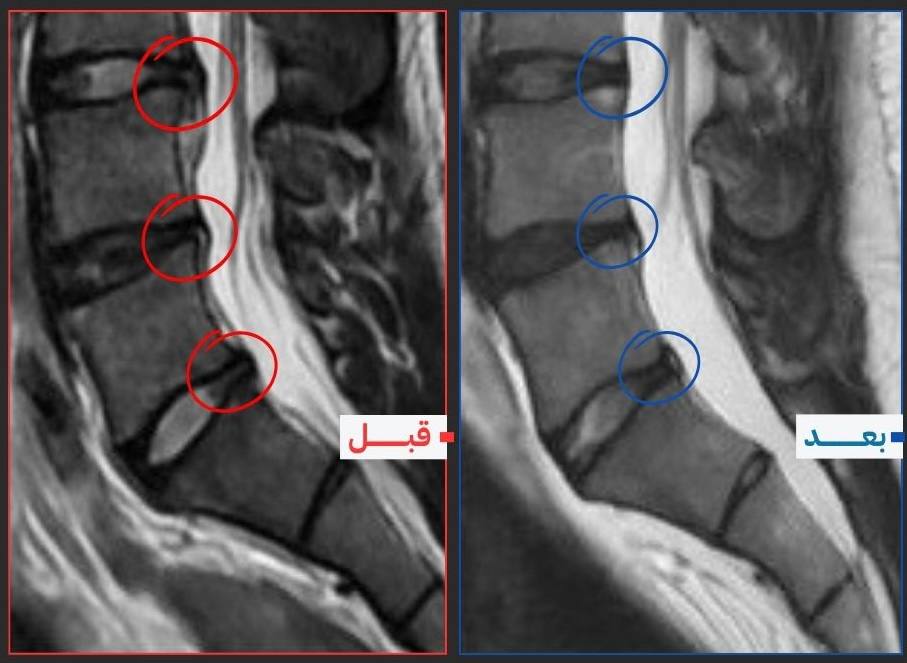

دليل مرئي على التعافي

صورة رنين مغناطيسي — قبل البرنامج وبعده

هذه صورة رنين مغناطيسي لمريض أتمّ البرنامج العلاجي. الفرق في حجم الانزلاق الغضروفي وتراجع الضغط على الجذر العصبي يظهر بوضوح بين الصورتين.

التحسن الوظيفي يسبق دائمًا التحسن الإشعاعي: كثير من المرضى يتخلصون من الألم قبل أن تظهر التغيرات في صورة الرنين. ما يهمك في البداية هو أن تعود لحياتك الطبيعية — والصورة تثبت أن الغضروف يستجيب.

النسيج الغضروفي لديه قابلية للتعافي حين تُزال الأسباب الميكانيكية المسببة للضغط — وهذا تحديدًا ما يستهدفه هذا البرنامج.